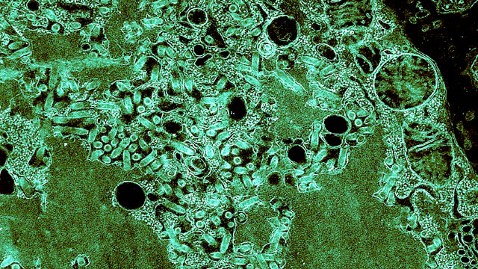

A microscopic image of the rabies virus. (Image credit: BSIP/UIG Via Getty Images)

The rabies virus, which is largely transmitted through dog bites and is responsible for over 55,000 human deaths around the world each year, is particularly fond of infecting the brain. It has the ability to catapult its victims into a downward psychotic spiral of delirium, hallucinations, and aggression that almost uniformly ends in death.